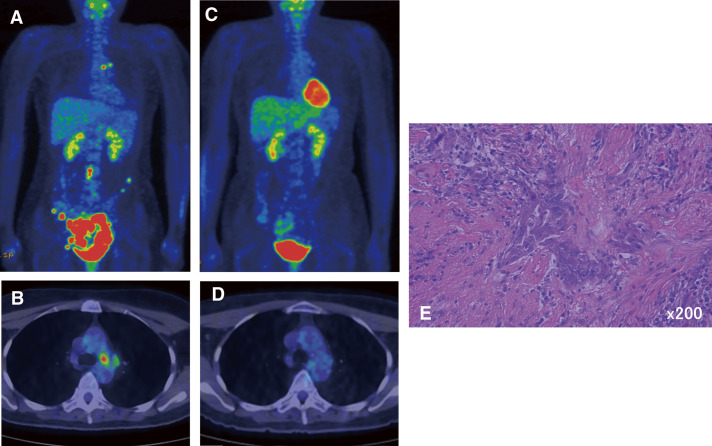

Case presentation: Case 1 was a 50-year-old woman diagnosed with ovarian cancer with mediastinal lymph node metastasis. After 4 courses of chemotherapy, a total hysterectomy, omentectomy, and mediastinal lymph node dissection were performed simultaneously. The patient is still alive 58 months after surgery. Case 2 was a 68-year-old woman who underwent a total hysterectomy after chemotherapy for endometrial cancer with multiple lymph node metastases. Forty-two months after surgery, mediastinal lymph node dissection was performed for metastasis of uterine cancer. She is still alive 75 months after surgery. Case 3 was a 69-year-old woman who underwent a hysterectomy for endometrial cancer. One year after surgery, she underwent thoracoscopic hilar and mediastinal lymph node dissection due to metastasis. Thirty-nine months have passed with no recurrence. Aggressive local control, particularly surgical resection of isolated hilar mediastinal lymph nodes in gynecological cancer, may contribute to prolonging patient survival.